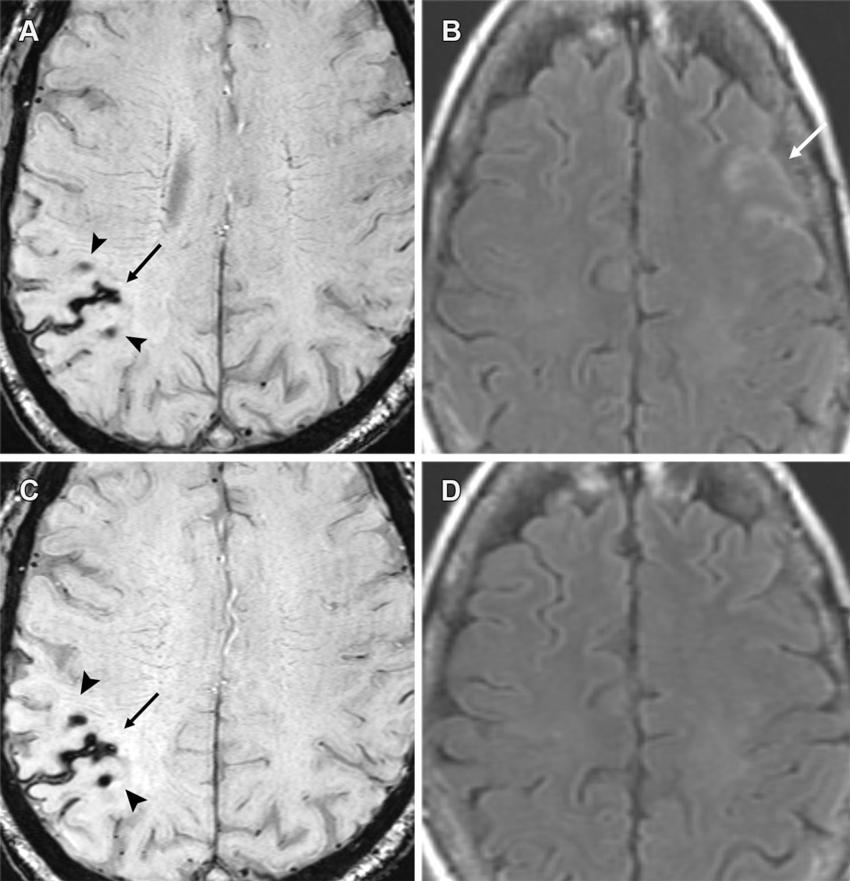

Figure 12. Moderate ARIA-E (edema) and ARIA-H (microhemorrhages, superficial siderosis) in a 60-year-old woman with headaches receiving aducanumab therapy. (A, B) Baseline MRI was unremarkable, with sequential MRI performed at 4 and 8 weeks after full dose. Axial T2*-weighted GRE (A) and FLAIR (B) MR images from the 4th-week examination show a new area of superficial siderosis (arrow in A), two microhemorrhages (arrowheads in A) in the right parietal convexity, and a subtle area of effusion (arrow in B) along the left frontal sulci. Therapy was suspended given the moderate radiographic findings and mild clinical symptoms. (C, D) Follow-up axial MR images at 8 weeks show stable hemorrhagic changes (arrow and arrowheads in C) on the T2*-weighted GRE image (C) with complete resolution of effusion on the FLAIR image (D). Superficial siderosis is the least common manifestation of ARIA and can be symptomatic, frequently requiring temporary or complete cessation of therapy.

High-res (TIF) version